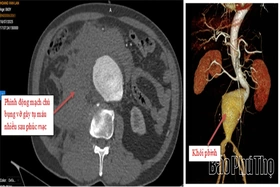

baophutho.vn Khoa Phẫu thuật Tim mạch – Lồng ngực, Bệnh viện Đa khoa tỉnh Phú Thọ vừa chạy đua với thời gian phẫu thuật cứu sống người bệnh H.V.L 65 tuổi,...

baophutho.vn Bệnh viện Đa khoa tỉnh vừa tiếp nhận một trường hợp hy hữu, người bệnh B.T.M, 71 tuổi, trú tại Hạ Hòa, cùng lúc bị sỏi mật gây tắc ống mật chủ...